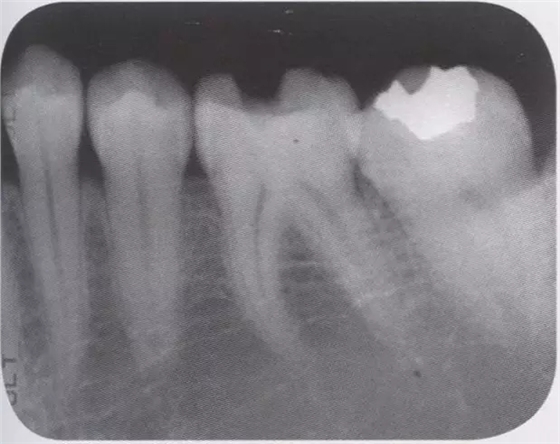

1、嵌體和高嵌體 在磨牙區(qū)域,由于牙齒近中面以及遠中面的傾斜程度不同,常會遇到分離困難的病例。例如,智齒的近中根傾斜,引起鄰牙根間隙過窄的情況。相鄰牙齒的近中傾斜,牙冠進入被處理牙倒凹處的情況(圖2、3)。以上情況,鄰接面由于齲齒形成窩洞,即便是運氣好在齦下做了分離,也會因為出血造成取模困難、頰舌的成形變大。所以采取以下處理措施。 1、術(shù)前拍攝牙片,根據(jù)牙根的傾斜判斷有沒有引起鄰牙根間隙過窄的情況。若沒有傾斜,就是簡單病例。 2、若智齒沒有對合牙,也考慮拔除智齒。 3、鄰接面用樹脂填充之后,用間接法進行烤瓷嵌體或烤瓷高嵌體修復(fù)。 1、貼面治療 對于變色牙齒進行貼面治療的情況下,牙頸部觀察無變色的情況下,可直接在齦上做成形。普通成形深度能夠保存牙釉質(zhì),因而判斷為簡單病例。(圖4) 如果牙頸出現(xiàn)變色,就需要進行齦下成形,難度增加。如果也存在前突問題,為改善變色貼面不能做厚,因而難度會更高。如果希望糾正前突、改善變色,則需要增加切削量,甚至可能進行拔髓。另外,由于粘接對象主要是牙本質(zhì),因而需要格外注意。

圖1 智齒向遠中傾斜病例

圖2智齒嵌入被處理牙鄰接面的倒凹,即便分離成功,成形范圍也會變大。

圖3鄰接面成形困難的病例。如圖所示右下7近中傾斜,窩洞成形的遠中側(cè)有缺損(上左),所以遠中部需要在齦下做很深的成形(上右),因而選擇在遠中先進行樹脂填充后(上右)。進行MO窩洞修整后做全瓷嵌體試戴(下)。